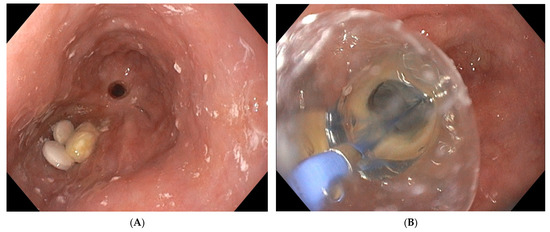

5.2. Intra-Procedure Difficulties

5.3. Post-Procedure Difficulties